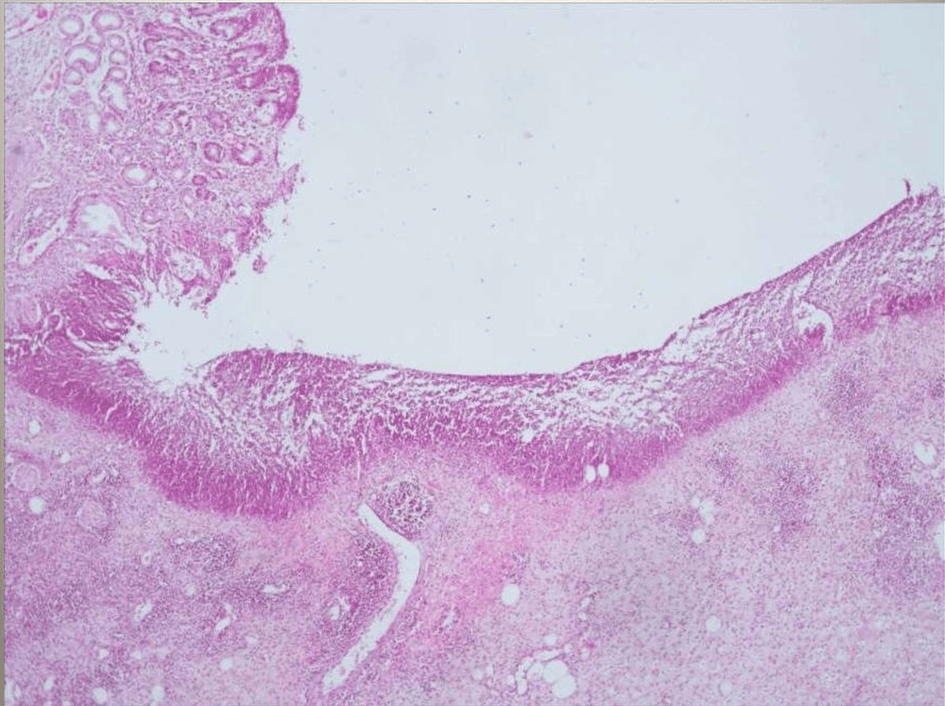

Most diverticula occur in the sigmoid colon, the curved part of the large intestine closest to the rectum, and they tend to become more numerous as we age.The inflammation may be local (just in the area of the diverticulum), or may spread to the abdominal lining (peritoneum), called peritonitis. Small (microscopic) or large perforations (holes in the intestinal wall) occur in 15 to 20% of people who have diverticula.